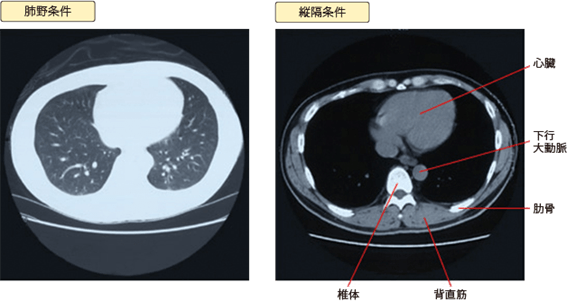

CT画像の種類

診察室で胸部のCTを見せられると黒っぽいものと白っぽいものがあることに気づかれると思います。白いほうを肺野条件、黒いほうを縦隔条件といいます。ほとんどの場合、同じデーターを2種類の出力で見せているのです。

このときに見たいものをある程度強調しないと見落としが発生します。そこで、肺の中の細い血管、気管支、肺胞(肺を構成している小さな袋です)などを検討するためにその部分を強調してフィルムに出力し、白っぽく見えるのが肺野条件です。

一方、心臓、大動脈、リンパ節、食道、脊椎骨などが集中している縦隔の状況を確認するために出力し、黒っぽく見えるのが縦隔条件です。